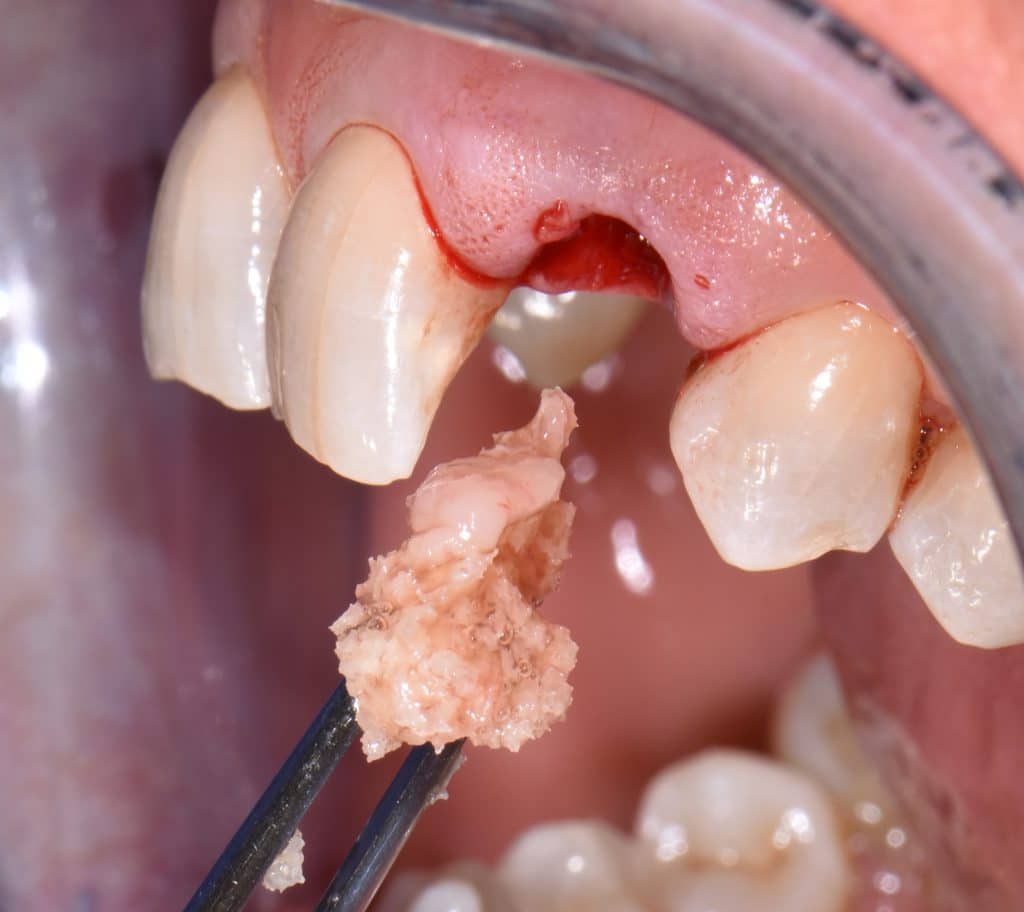

La pz N.G. di anni 52 (ASA 1) viene visitata nel mese di settembre 2017 per la mobilità ed inestetismo dell’elemento protesico 22, (foto iniziali sequenza 1) si evidenzia una frattura parziale della radice, si decide per l’estrazione ( foto sequenza 2) e sostituzione dell’elemento con un restauro implanto-protesico. Purtroppo la scarsa quota ossea apicale all’alveolo post-estrattivo (foto 2 rx) e l’alta valenza estetica dell’elemento ci rende cauti e si programma una socket preservation post estrattiva con l’ausilio delle membrane di prf (foto prf e socket sequenza 3 e 4). Durente i 5 mesi di guarigione la pz porta una protesi parziale mobile (foto 5,2) , a guarigione del sito post estrattivo si evidenzia una buona conservazione dei volumi osseo-gengivali,(foto guarigione sequenza 6) se pur presente una recessione distale all’elemnto 21.Nel mese di febbraio 2018 si procede all’inserimento di un impianto max-stability 3,75x12mm disegnando un lembo anticipato palatino per consentire un aumento dei tessuti vestibolari suturando con tecnica rool flap e trasformando l’elemento parziale mobile in una corona singola a carico immediato sul moncone temporameo applicando i concetti protesici bopt , (foto impianto moncone protesi provvisoria sequenza foto 7-8-9). Durante il periodo di maturazione dei tessuti molli vengono apportate opportune modifiche ai profili del provvisorio al fine di dare maggior spazio al tessuto gengivale, ( fotosequenza 10).Dopo circa 2 mesi dal protesizzazione provvisoria si è proceduto alla realizzazione del manufatto protesico con tecnica chair side sirona con l’ausilio del t-base (foto sequenza 11-12-13), realizzando in una sola seduta una corona in disilicato, ottenendo un risultato più che soddisfacente (Foto 14). Nel controllo a 3 mesi dal carico definitivo si apprezza la perfetta conservazione dei livelli ossei e gengivali. (foto sequenza 15).concludo con un follow up a 18 . Tengo a sottolineare che un caso come questo è stato conducibile con buoni risultati solo grazie alla piena fiducia della pz e alla sua massima motivazione e collaborazione. Ad oggi la pz sorride soddisfatta del risultato. E questo rappresenta la massima ricompensa di chi dedica tutto se stesso alla professione.